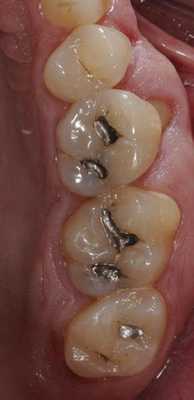

Пациент обратился за помощью с несколькими основными жалобами, главной из которых являлась эстетическая дилемма: ему не нравился цвет, размер и форма зубов (фото 1). При этом он также желал по возможности закрыть диастему между 10 и 11 зубами. Он также был обеспокоен «объемом» собственной улыбки и хотел расширить форму зубной дуги так, чтобы улыбка казалась более полной. Во время стоматологического осмотра было установлено, что пациент имел умеренную степень стирания режущих и окклюзионных поверхностей, легкую генерализированную форму рецессии с локализированной умеренной рецессией в области первых моляров верхней челюсти. Большинство боковых зубов имели амальгамные реставрации небольших и средних размеров с признаками вторичного кариеса. На 18 и 29 присутствовали металлокерамические конструкции. Все передние зубы верхней челюсти и несколько передних зубов нижней челюсти имели композитные пломбы в интерпроксимальных зонах, которые со временем изменили свой цвет.

Фото 15-21. Последовательность клинических процедур: вид до вмешательства, вид прототипа, удаление прототипа, дефектных амальгамных пломб и остальных реставраций, нанесение кариес-маркера, запечатывание дентина и заполнение поднутрений, установка окончательных реставраций.